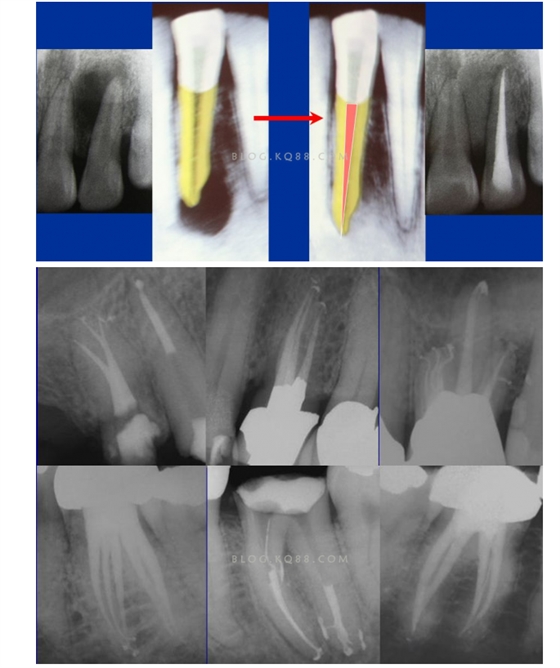

1簡化難度 一個牙齒的根管治療難易程度不單單是根管的彎曲、細小、牙位、是否再治療決定的,開髓的直線進入和根管口的預(yù)先恰當(dāng)處理可以簡化很大的難度,開髓是根管成敗的基礎(chǔ)。對于彎曲根管冠部的直線入口就顯得尤為重要,冠部良好的直線入口可以避免側(cè)穿、臺階、遺漏根管等問題的發(fā)生,冠部直線入口形成的良好情況,取決于醫(yī)生的理念和合理的器械選擇。開髓孔的大小不是由醫(yī)生和患者的意愿決定的,而是由要治療牙齒的髓腔大小決定的。

2相信有更多的根管存在 相信根管的數(shù)目比我們想象的多,根管系統(tǒng)的復(fù)雜程度比我們想象的見到的要更復(fù)雜,我們只有用盡所有努力和辦法才可能達到預(yù)期目標(biāo),對于上 牙合 6的MB2來說過去是偶爾有,現(xiàn)在是偶爾沒有,各種文獻報道的比例也不一致,我在培訓(xùn)班醫(yī)生帶來的離體牙中幾乎沒有見到?jīng)]有的,臨床中也是一樣。對于尋找的方法來說,我覺得相信有才是最重要的,首先相信一定有就會想各種辦法,找到的幾率就會更多。如果有條件在顯微鏡和超聲的配合下效率會更高。

5、預(yù)備到多少號結(jié)束根管預(yù)備理想的情況應(yīng)該預(yù)備到多大錐度,多少號,預(yù)備后根管空間是金字塔還是埃菲爾鐵塔。專家經(jīng)過離體牙根尖切片研究發(fā)現(xiàn)根尖狹窄部遠比想象的要大,如果根管預(yù)備太小就會殘留感染物,根管的部分空間就不會預(yù)備到,殘留的感染物就會造成治療效果達不到預(yù)期目標(biāo)。只有做到了充分的預(yù)備,盡可能的多沖洗才會有好的結(jié)果。

根管治療要做到看清楚,去干凈,充恰滿,封嚴密,就會達到期望的結(jié)果。2200年前的病例只充填了冠1/3可以理解、可以接受;2200年后的今天我們有先進的設(shè)備和材料,就要充填出大錐度高密度的完美結(jié)果。理念決定技術(shù),標(biāo)準決定技術(shù)的提高和進步。